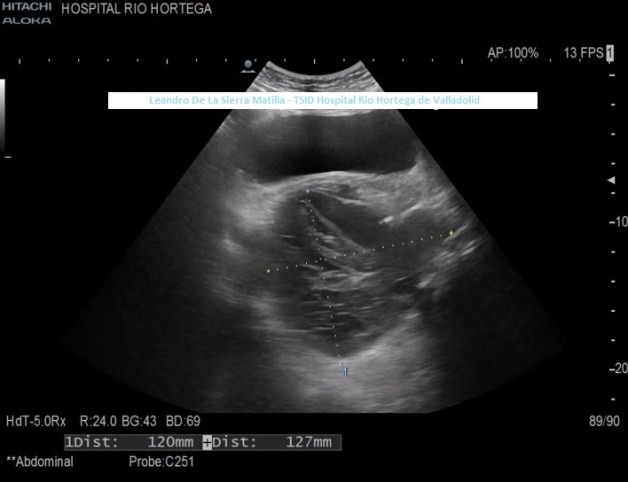

Un aperitivo de estos hallazgos en las imagen 7, sonde observas dos lesiones unidas, exofíticas, una quística y otra no, muy difícil de visualizar por las características del paciente y que debió ser diagnosticado por CT. Las flechas amarillas marcan una lesión quística, las rojas una lesión no quística, lo ves mejor en la imagen 8 donde puedes ver ambas medidas mejor definidas y medidas.

7

8